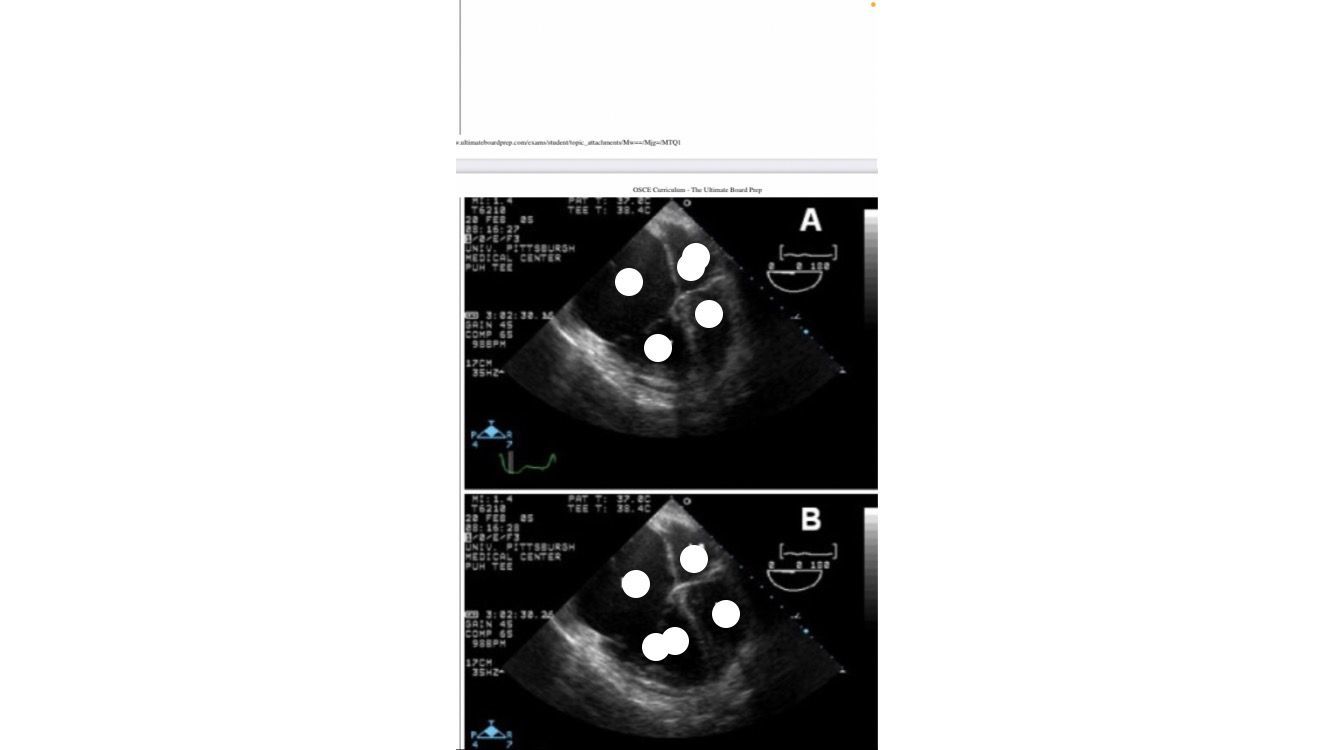

Mid esophageal RV inflow and outflow

TRICUSPID NOT MITRAL VALVE

Bicaval view

air embolism in right atrium

PFO